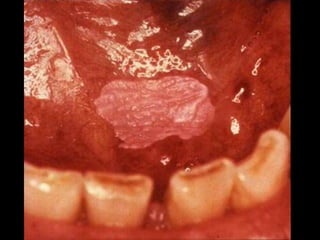

“Irritation” Fibroma

PYOGENIC

GRANULOMA

“Canker” sore = Aphthous ulcer